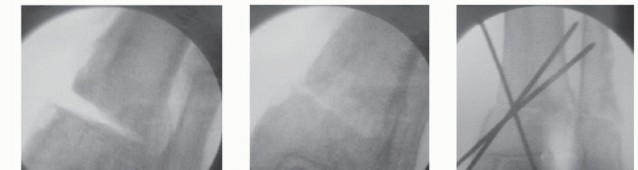

TECH FIG 1 • Medial closing wedge supramalleolar osteotomy. A. Using a preoperative radiograph, the center of rotation of angulation (CORA) is located at the intersection of two lines that represent the mechanical axes of the proximal and distal segments. B. Under fluoroscopy, a Kirschner wire is inserted to the tibia perpendicular to the mechanical axis and a second Kirschner wire is inserted parallel to the ankle joint line intersecting the first wire, ideally at the apex of the deformity. C,D. Guide pin wires used to perform a closing medial wedge osteotomy. Pin A has been inserted to the tibia perpendicular to the mechanical axis and pin B has been inserted parallel to the ankle joint line, intersecting pin A at the apex of the deformity. E. The cut wedge. The pins have been used as a guide for the tibial cuts, whereas the size of the wedge has been determined during the preoperative planning. (continued)

- TECH FIG 1 • (continued) F. Fluoroscopic view of the resected wedge. G. Fluoroscopic view of the closed osteotomy. H,I. Fluoroscopic AP and lateral views of the provisionally fixed osteotomy with Kirschner wires. J. Photo of the applied periarticular plate. Note the excellent fit on the distal tibia. K. The applied periarticular plate after completion of fixation with three screws in the distal segment. L. Fluoroscopic view of the osteotomy after completion of fixation.

We routinely use Kirschner wires to define our proposed osteotomy; for an opening wedge osteotomy, we use a single Kirschner wire, but for the medial closing wedge osteotomy, two Kirschner wires are required to define the tibial wedge resection. Under fluoroscopic guidance, insert the first Kirschner wire perpendicular to the mechanical axis and the second parallel to the ankle joint, intersecting the first Kirschner wire at the apex of the deformity. The size of the wedge has been determined during the preoperative planning, and the Kirschner wires are positioned 1 to 2 mm wider than the proposed osteotomy, so they can be left in place as a guide for the saw cuts. Although the Kirschner wires define the osteotomy in one plane, the surgeon must also orient the saw blade perpendicular to the tibial shaft axis when performing the osteotomy. With the anterior and posterior soft tissue and neurovascular structures protected, we routinely use a broad oscillating saw, constantly irrigating the blade with cooled

sterile saline or water to limit osteonecrosis. Ideally, a thin cortical bridge and periosteal sleeve on the opposite cortex will be preserved to allow for a greenstick-like closure of the osteotomy that facilitates maintenance of alignment and enhances stability. However, when the osteotomy is intentionally performed at a level different than that of CORA, then the opposite cortex must be violated to allow the distal segment to be translated.

After removing the resected wedge and performing appropriate translation of the distal segment, close the osteotomy and provisionally fix it with Kirschner wires. The provisional fixation may be guidewires for intended cannulated screws or it must be positioned so as not to interfere with the definitive fixation.

Assess alignment of the tibia and ankle fluoroscopically, both in the AP and lateral planes.

Several dedicated low-profile periarticular plating systems for the distal tibia are marketed, both locking and nonlocking. The majority of these plates were designed for the contours of the physiologic tibia. With a wedge resection, the fit is typically acceptable but may not be perfect. Locking plates may provide optimal stability, but if the osteotomy is not fully closed, these may in fact delay or even hinder healing.

Nonlocking plates, in our opinion, allow for a small amount of settling at the osteotomy with weight bearing, potentially facilitating healing. (If additional stability is required, then cannulated or solid screws may be used from the tip of the medial malleolus across the osteotomy. Alternatively, a second plate may be added anteriorly on the tibia to provide rotational control to the tibia; however, this requires greater soft tissue dissection.)

We do not routinely apply fixation to the fibula, but if additional stability is required, then we apply a low-profile fibular plate.

Final fluoroscopic images in the AP and lateral planes confirm proper alignment, apposition of the osteotomy, and position of hardware. -